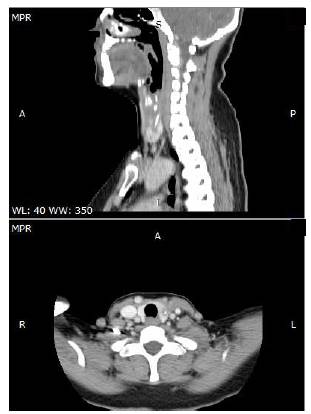

Se presenta el caso de una paciente de 53 años de edad, sin antecedentes de importancia, con un cuadro clínico de tres meses de evolución de odinofagia posterior a la ingestión accidental de una espina de pescado. Ingresó con un reporte de una ecografía extrainstitucional que había demostrado un cuerpo extraño alojado en el lóbulo tiroideo izquierdo en relación con la musculatura del esófago. Se le tomó una tomografía computa-rizada (TC) de cabeza y cuello que mostraba una imagen hiperdensa lineal de 2,6 cm de longitud en la misma localización.

Ante la sospecha de un cuerpo extraño alojado en las vías digestivas, el examen inicial suele ser una radiografía simple de cuello, por su disponibilidad, aunque esta solo alcanza el 80 % de sensibilidad. En combinación con la TC, alcanza el 100 % 6,9 y, además, permite guiar el enfoque hacia la eliminación de la espina de pescado. Con estos dos estudios, se puede demostrar la ruta migratoria y se detecta un buen número de cuerpos extraños delgados, pequeños y mínimamente calcificados 5,7,10,11 (figura 2).